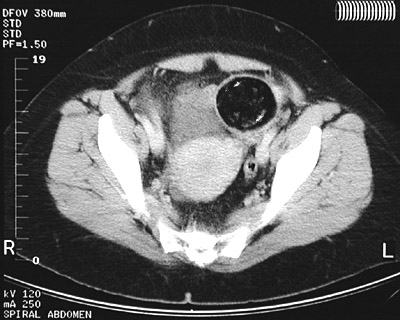

![]() | The CT scan of the pelvis in axial view demonstrates a large discrete mass with variegated contents, including soft tissue densities and calcification. This is a mature cystic teratoma ("dermoid cyst") of the left ovary. Most of the contents have the same attenuation as the abdominal fat, indicative of the fact that much of a dermoid's contents consist of oily fluid. |